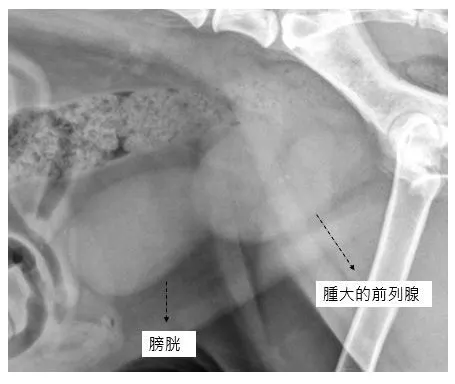

A:前面有說到腫大的前列腺有可能會壓迫到直腸,因此最經濟實惠的檢查方式就是直腸觸診,獸醫師會用手指伸進直腸內探查有沒有前列腺腫大的問題(當然是要戴手套拉),不過手指頭能夠檢查的範圍畢竟有限,因此大部分的時候都還是得靠X光或超音波全面性地檢查前列腺的大小與構造是否異常。

麻煩的是,有些情況下單靠X光與超音波也無法判斷腫大的前列腺是到底是良性增生或是惡性腫瘤,這時就會需要安排細針採樣或粗針切片採樣取得部分的前列腺細胞或組織進一步化驗。如果懷疑有發炎的話還需要抽血檢查白血球數值是否過高,也會需要做尿液分析與細菌培養檢查確認是否有感染的問題。